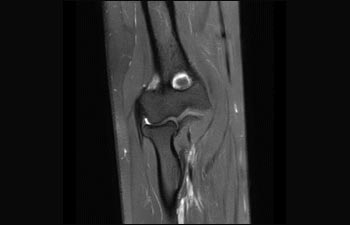

Sehen Sie selbst, was die ersten Nutzer von Ingenia Prodiva 1.5T über ihre Erfahrungen mit dem System und dessen Auswirkung auf ihre radiologische Praxis berichten.

Finden Sie die richtigen klinischen Applikationen für Ihre Anforderungen

1 Basierend auf einer internen Studie zum Vergleich des Workflows mit einem Achieva System 2 ComforTone ist ab Q4 2017 für den Prodiva 1.5T erhältlich. 3 Basierend auf einer internen Vergleichsstudie mit dem Arbeitsablauf des Achieva MRT-Systems bezüglich einer Mischung aus Gehirn-, Wirbelsäulen-, MSK- und Körperuntersuchungen 4 Normaler Betrieb ist definiert als eine typische Untersuchung mit ununterbrochener Verfügbarkeit von Strom und Magnetkühlung und ohne Wartungsmassnahmen. 5 Abhängig von den vertraglichen Ansprüchen und der Verfügbarkeit 6 „Andere MR-Systeme“ bezieht sich hier auf Ganzkörper-MR-Systeme mit 60 cm und 1,5 T.